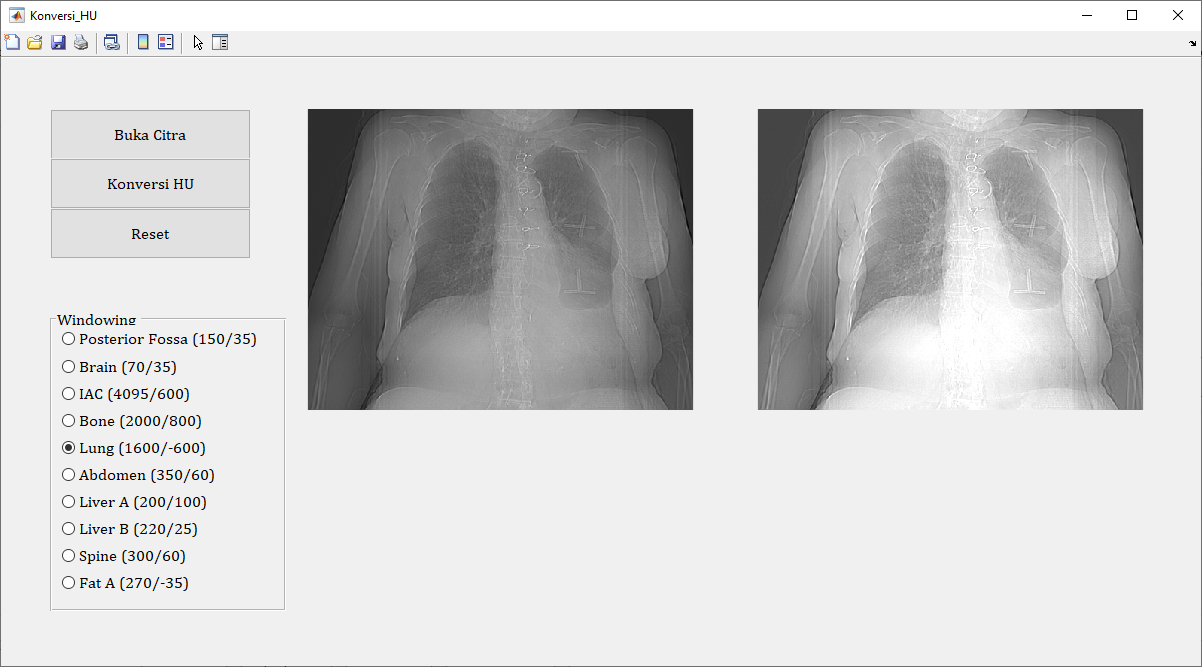

4. Menampilkan Citra HU

Terakhir, kita dapat menampilkan citra HU yang telah dikonversi untuk analisis lebih lanjut atau keperluan diagnostik.

% Menampilkan citra Hounsfield Unit (HU)

imshow(image_HU, []);

title('Citra Hounsfield Unit (HU)');